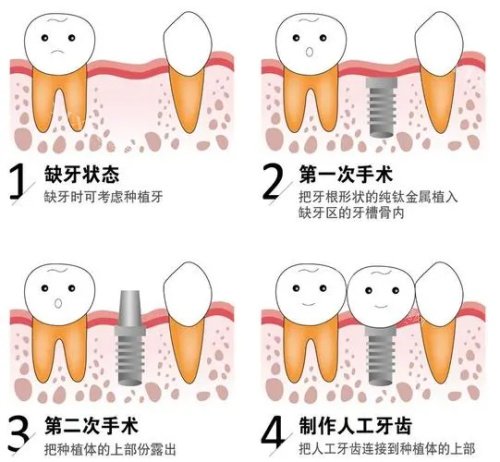

贝乐美口腔为二胎妈妈们提供了多种优惠套餐,尤其是针对家庭客户的综合治疗套餐。比如,牙齿矫正套餐价格从9800元起,比单次治疗能省下一半的钱。此外,医院还经常推出限时优惠活动,如种植牙套餐在活动期间价格更加实惠。这些套餐不仅价格优惠,还能根据家庭成员的不同需求进行个性化定制,让二胎家庭在享受优质医疗服务的同时,大大节省了开支。